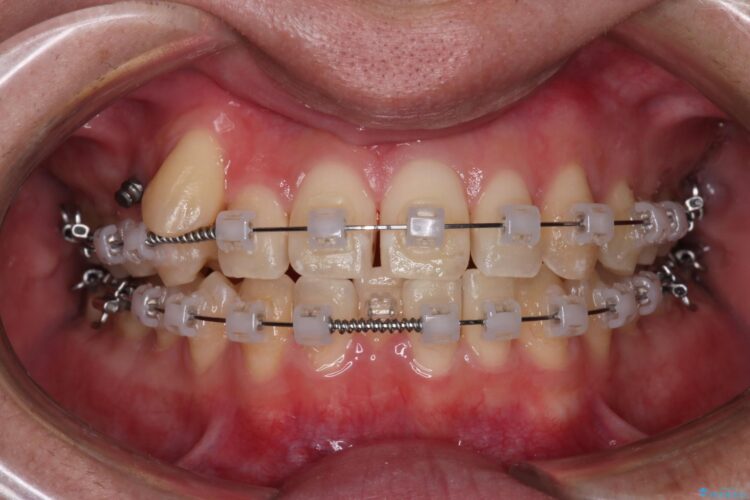

精密検査の結果、抜歯の必要はないと判断しました。臼歯を遠心移動させ、歯列をワイヤーで整えることでスペースを確保し、IPR(歯と歯の間を削る処置)を加えて歯並びを綺麗にする治療計画を立てました。

歯の移動にオープンコイルとMI(歯肉に埋入するネジ)を用いました。